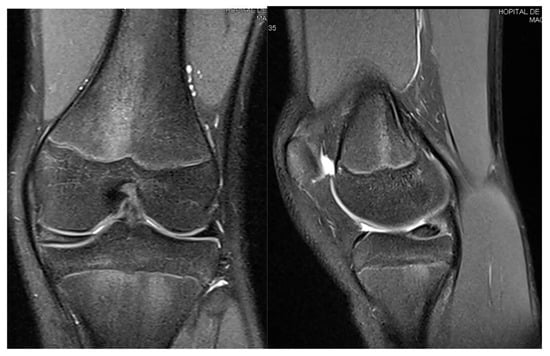

3.2. Case 2—S.C.S.

| S.C.S. | 13 | Left | Pain, occasional locking, normal ROM | Dancing | 1 surgery: partial meniscectomy and suture for horizontal tear (13) | 6 months: symptom-free, full ROM, resumed dancing |